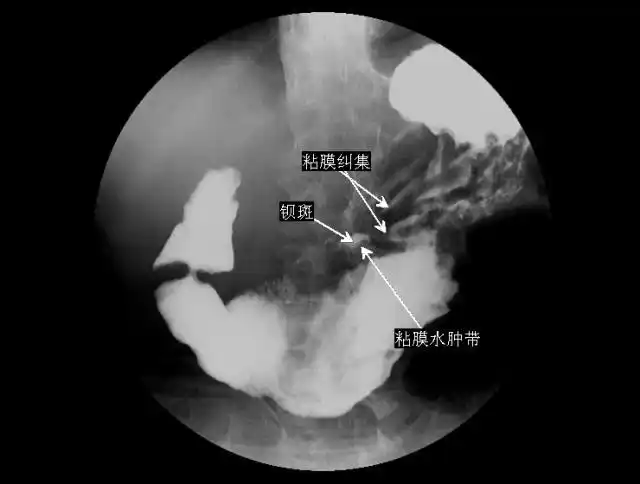

典型陈旧性胃溃疡

消化性溃疡